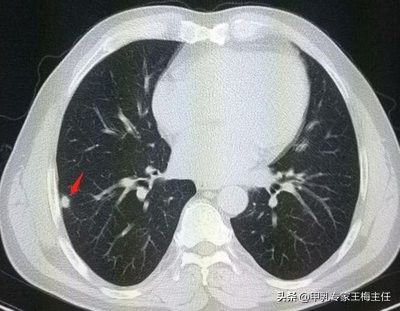

大概是去年上半年的时候,常女士检查出肺部有一个大约5.3mm的结节。当时的医生说看问题不大,定期复查就行了。

我经过详细的辩证后,认为常女士的肺结节完全可以通过中医治疗得到消除,于是开方治疗。 两个月后,常女士去医院复查肺部CT时,结节已缩小到2毫米,十分惊喜。积极配合又治疗了2个月,再次复查时,结节已经完全消失了,后来继续调理了一段时间体质,到现在一切正常。